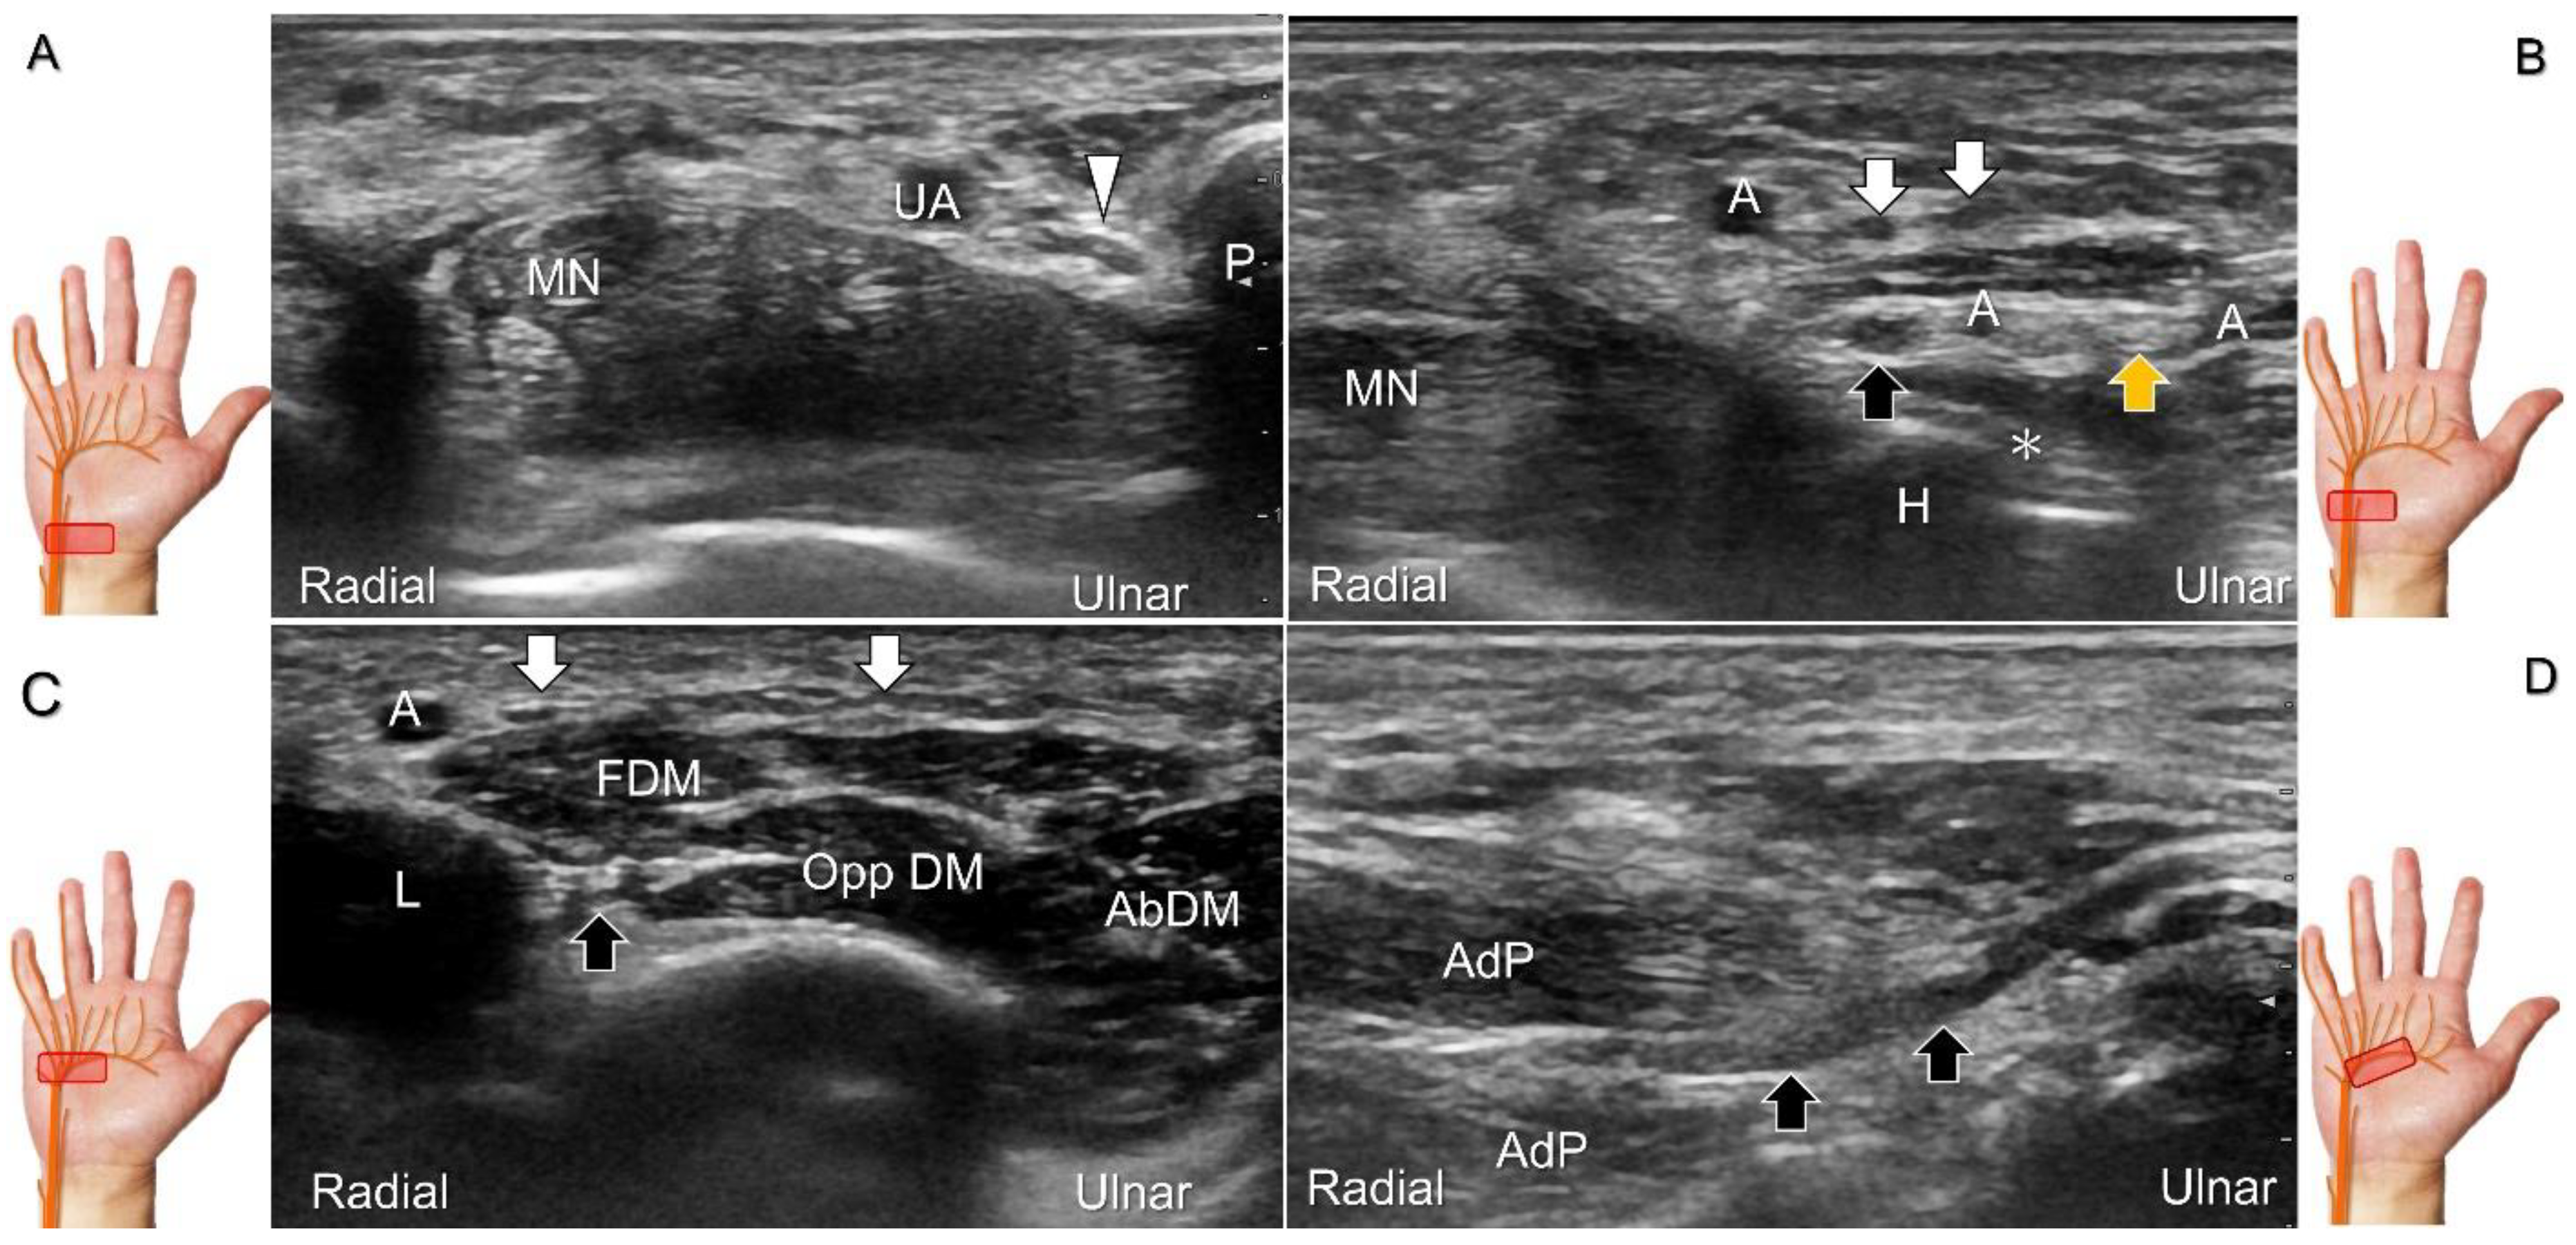

Scanning Technique

To locate the Guyon’s canal, the transducer is placed along the axial plane on the volar wrist with the forearm supinated. This will reveal the ulnar nerve and artery within the canal (Figure 13A). To investigate the nerve’s long axis, the transducer is rotated 90 degrees. By moving the transducer toward the finger, the superficial and deep branches can be seen. Between the pisiform and hamate, the superficial and deep branches (along with their accompanying vessels) can be visualized as separated by the fibrous arch of hypothenar muscles, respectively (Figure 13B) [39].

The superficial branch divides into two palmar digital nerves. They run superficially along the little finger and half of the ring finger. The deep branch, on the other hand, can be observed between the flexor digiti minimi brevis and opponens digiti minimi muscles before it penetrates the deep aspect of the palm (Figure 13C). By pivoting the transducer, the physician can display the long axis of the deep branch, extending all the way to the segment within the adductor pollicis muscle (Figure 13D).

Figure 13. Sonographic imaging (short-axis view) shows the ulnar nerve within the Guyon’s canal (A), separation of branches beside the pisohamate hiatus (B), deep branch of the ulnar nerve located between the hypothenar muscles distal to the hook of the hamate (C). Long-axis view (through pivoting the transducer) shows the segment of the deep branch within the adductor pollicis muscle (D). Arrowhead: ulnar nerve; white arrows: superficial branch of the ulnar nerve; black arrows: deep branch of the ulnar nerve; orange arrow: branch of the ulnar nerve to the abductor digiti minimi; *: pisohamate ligment MN: median nerve; UA: ulnar artery; P: pisiform; H: hook of hamate; A: artery; L: lumbrical muscle; FDM: flexor digiti minimi brevis muscle; Opp DM: opponens digiti minimi muscle; AbDM: abductor digiti minimi muscle; AdP: adductor pollicis muscle.